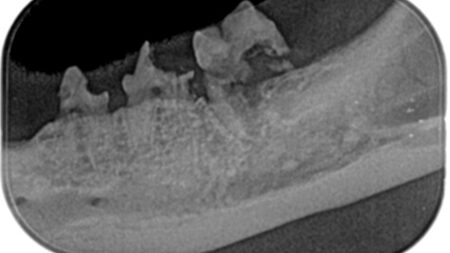

Left mandibular premolars and molars, 8 yr M/N Domestic Short Hair cat.